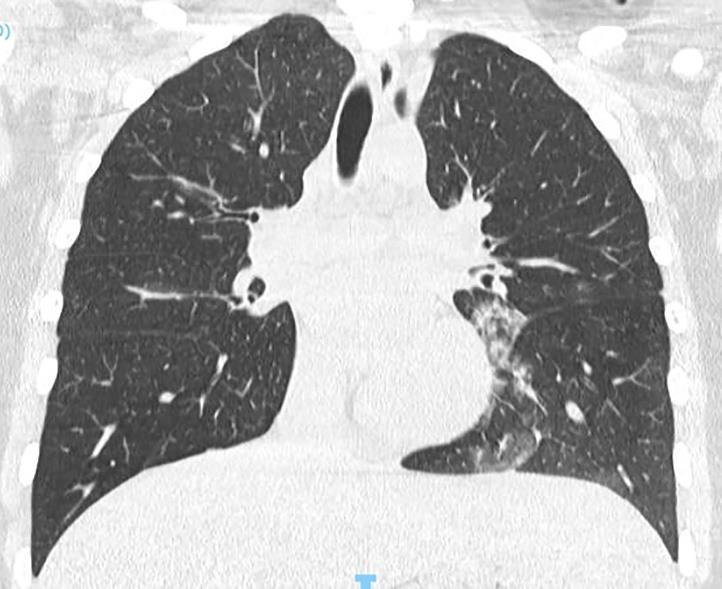

Acute Pediatric COVID-19: CT

21 Imaging of Covid 19 infection in children

3 Phases

Early: "Halo" sign

Local infection

Progressive: Diffuse GGO

Developed: Consolidation

Surr vasc congestion

Inflammation - adj alveoli

Alveoli fill with fluid/cells